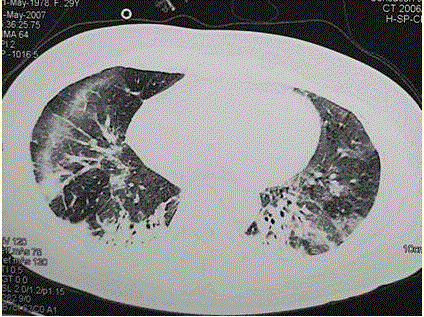

问题 患者女,29岁。间断干咳10年余,加重4个月,伴进行性呼吸困难1个月。病程中出现双手及双足非凹陷性肿胀、双侧膝关节及双侧肘关节对称性肿痛,面部出现细小红色丘疹。体检:T 36.5℃,P 88次/min,R 22次/min,BP 110/75 mmHg,SpO 93%(自然)。额部、前胸及后背散在红色小丘疹,双肺呼吸音增强,双肺中下肺野可闻及爆裂音,右肺明显。胸部CT 如图所示。 该患者最可能的诊断是(提示 患者无发热,血常规正常,痰培养阴性 。)

选项 A.肺泡蛋白沉积症 B.军团菌肺炎 C.特发性间质性肺炎 D.结缔组织病肺受累 E.肺部恶性肿瘤 F.结节病 G.社区获得性肺炎

答案 D